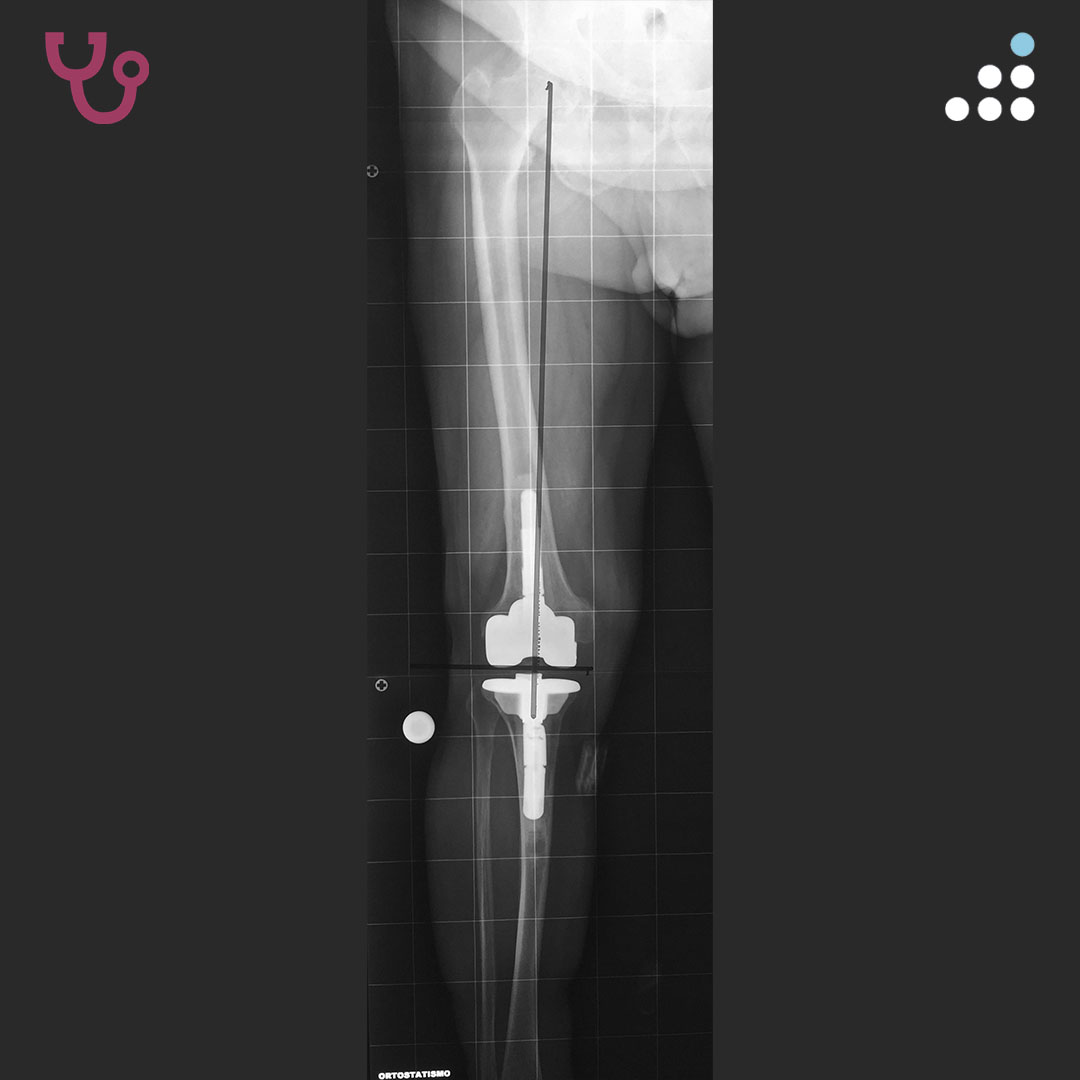

I wanted to see how good the AI is reading xrays. I uploaded this Xray and gave this prompt: What is the Anderson Orthopaedic Research Institute (AORI) Classification?

Femur: AORI Type 1 – metaphyseal bone stock globally preserved, intact cortical rims, no large cavitary or segmental defects; long cemented stem not clearly bridging a major metaphyseal void.

Tibia: AORI Type 2A – proximal metaphyseal bone loss predominantly on one side with thinning/osteolysis, but overall cortical rim preserved and remaining metaphyseal bone capable of supporting a stemmed component.

Overall: AORI femur 1 / tibia 2A, based on AP view only; final classification subject to confirmation with lateral and intra-operative findings.